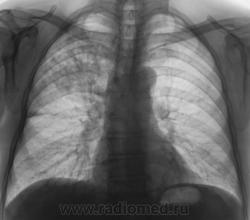

Произведена рентгенограмма в прямой стандартной проекции и томограммы в стандартных срезах.

«Пневмония», сразу показалась какой-то «фердиперсовой», с учетом лечения в стационаре ранее, довольно хорошего самочувствия пациента и наличием весьма «убогой» клиники. После проведения исследования было рекомендовано провести противовоспалительное лечение, исследование мокроты с целью проведения дифференциальной диагностики, рекомендована консультация фтизиатра.

Мы в протоколе, конечно, отметили, о возможности инфильтративного туберкулёза, д/д ряд даже не дали.

Пациент 4 месяца, по полной программе отлежал в областной конторе, ЦВК утвердило «инфильтративный». После выписки был направлен под надзор фтизиатра по месту жительства. Ниже иллюстрации после выписки.

Снимки сегодня.